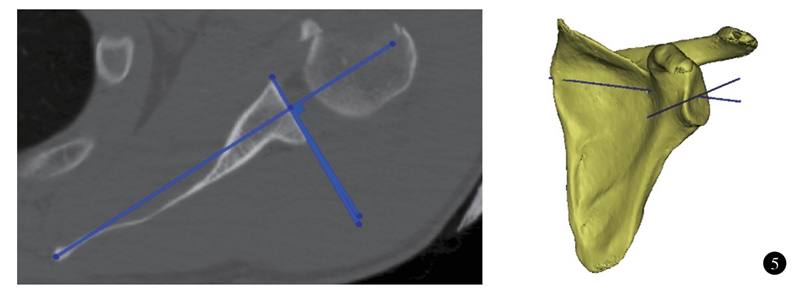

测量肩胛盂前后方向上的倾斜有多种方法。传统二维测量方法是获取患者的二维CT数据,做肩胛骨最内侧的点至肩胛盂中心的连线(friedman线) ,同时做肩胛盂前缘和后缘的连线(中关节线) ;中关节线和Friedman线垂线之间的夹角即为肩胛盂前后方向的倾斜角度(图5) 。根据成角的方向,又分为前倾(anteversion) 和后倾(retroversion)。这种测量方法被认为是测量肩胛盂前后方向的倾斜的金标准。但它没有设立坐标系,不是三维立体测量;肩胛骨的方向、冠状位或矢状位的旋转会影响测量的精度。最新文献建议应使用三维CT测量肩胛盂前后方向的倾斜。Kwon等以肩胛体最低点、肩胛盂中心和肩胛骨最内侧三点建立坐标系,并参考Friedman法测量肩胛盂前后倾(图5) ,发现三维CT能更精确评估测量肩胛盂前后方向的倾斜,具有更佳的可靠性。国外文献报道,正常人群三维CT测量肩胛盂前后方向的倾斜均值-4.5~2°;男女对比并未发现性别差异。汪华清等选取肩胛盂前后缘中点至肩胛骨内侧缘中点的连线作为参考线,测量了国人肩胛盂在前后方向上的倾斜,所得结果为(-0.03±4.66)°;其中男性为(1.20±4.87)°,趋于前倾;女性为(-1.84±3.71)°,趋于后倾。与西方研究结果不同,男女性之间比较差异有统计学意义。

图5 二维及三维CT测量肩胛盂前后方向的倾斜角度示意图。肩胛盂中心至肩胛骨内侧连线的垂线与肩胛盂前后缘之间的夹角;图中三维CT测量关节盂前倾角为0°